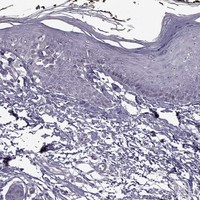

Enhanced - Orthogonal

Antibody staining mainly consistent with RNA expression data across 44 tissues.

LOW EXPRESSION

Skin 1

RNA expression: 17.3 nTPM